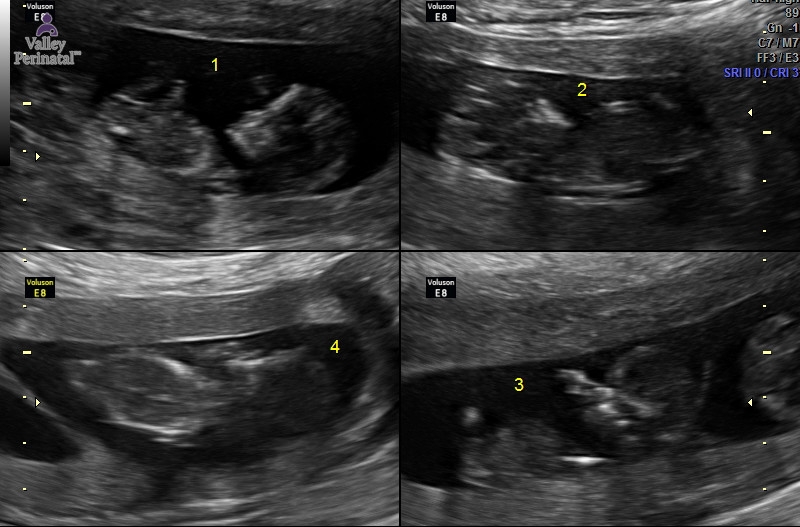

Sorry to be MIA these past few weeks, our big move from AZ to NH is next week so we've been crazy people lately! Today we had our NT scan with the specialist and everything went PERFECT. I was so worried so now that the appointment went well I feel like I can breath a little easier admist our crazy and hectic life we are currently living! Once we move things will be alot calmer and I'll be able to focus more on getting ready for these 4 babies! As usual I will include our most recent ultrasound from today. Baby C has earned the name of trouble maker due to not cooperating during the ultrasound and  taking up 45 minutes of the techs time trying to get he/she to move into the right position. The tech also thinks that baby A is a boy and baby B is a girl but I'm not sure if I fully believe her as I am only 12 weeks 3 days! Baby c and D weren't in the right position for her to make a guess of the gender.